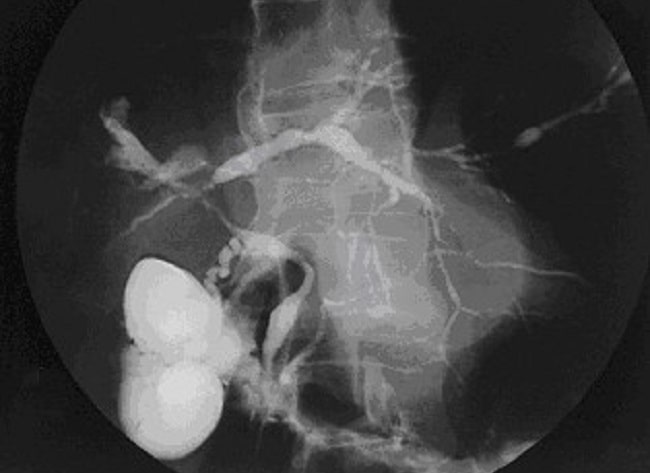

Intervensi: Subjek dipilih secara acak untuk mendapatkan intervensi laparoskopi kolesistektomi (n=185) atau laparoskopi kolesistektomi + kolangiografi intraoperatif (n=186). Prosedur laparoskopi kolesistektomi dilakukan dengan menggunakan teknik empat port standar. Sementara itu, prosedur laparoskopi kolesistektomi + kolangiografi intraoperatif dilakukan dengan penambahan injeksi meglumine diatrizoate (pengenceran 1: 1 dengan cairan salin normal) melalui kateter yang dimasukkan melalui sayatan kecil di duktus sistikus yang dibuat dengan gunting laparoskopi.

Deskripsi prosedur kolangiografi intraoperatif dijelaskan dengan baik dan dilakukan dengan bahan standar yang sama. Alat visualisasi anatomi bilier juga dideskripsikan jelas dan menggunakan standar yang sama. Namun, alat laparoskopi tidak dideskripsikan pada penelitian ini, sehingga tidak dapat diketahui apakah setiap operasi dilakukan dengan alat laparoskopi standar yang sama. Prosedur kolangiografi intraoperatif dilakukan dengan menggunakan gunting laparoskopi untuk membuat lubang kecil pada duktus sistikus, kemudian memasukkan kateter, dan menyuntikkan cairan salin normal dan meglumine diatrizoate dengan perbandingan 1: 1. Anatomi bilier divisualisasikan secara dinamis menggunakan mesin C-arm mobile yang dilengkapi dengan penguat gambar. Untuk prosedur laparoskopi kolesistektomi, hanya dijelaskan menggunakan teknik empat port standar, namun rincian alat apa saja yang dipakai tidak disebutkan.